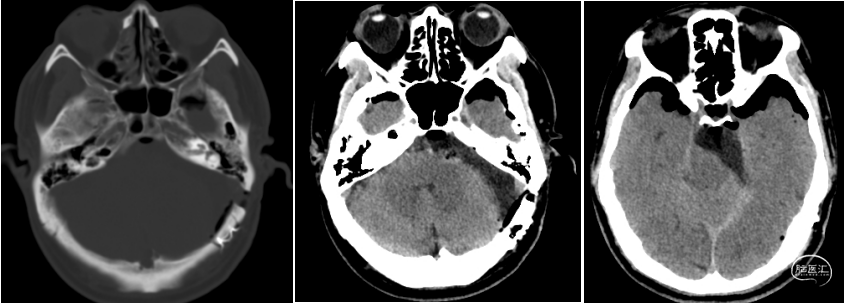

术前检查

![]()